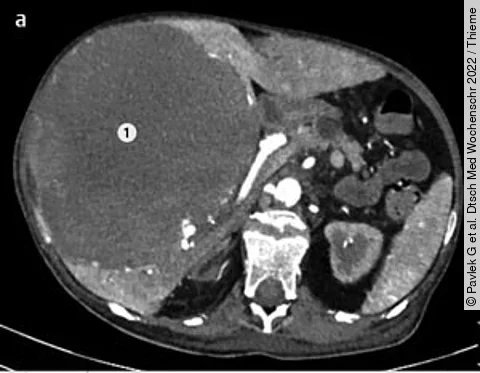

QuizAuflösung: 57-jährige Patientin mit Oberbauchschmerzen und Anämie

Befunde

Siehe großes Bild unten

1. Eine große fokale hypodense Leberläsion, welche die ganze rechte Leber einnimmt

2. Eine gute Vaskularisierung der Leberläsion

3. Computertomografisch zeigen sich Areale verschiedener Dichte innerhalb der Läsion